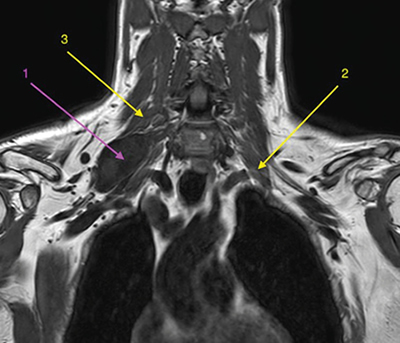

Figura 1

Figura 2